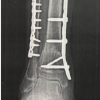

At the Tertiary Care Hospital in Bandra, Mumbai, 52 tibial shaft fractures were treated with tibial IMN between July 2019 and December 2020. The vast majority of tibial fractures were treated with a semi-extended technique, with the exception of grade IV arthrosis in the immovable PF joint (PFJ). Surgeons working alone performed all of the SP tibial IMN procedures. In this nonrandomized retrospective analysis, 52 patients (44 men and 8 women; mean age 47.2 years; range, 18–75 years) getting semi-extended care through the SP route were included in the study. For every patient, information on gender, age, limb side, and fracture classification was noted. The AO system was utilized for the classification of fractures. Written informed consent was given by each patient. Within 48 h of arriving at the emergency hospital, all fractures were treated by SP route tibial IMN. Initially, the patients received spinal anesthesia. Before the procedure, a pneumatic tourniquet was inflated. Next, the leg was prepared in a semi-extended posture with 15° of flexion. An SP midline incision was made 3 cm from the superior to proximal pole of the patella. The quadriceps tendon was incised along the midline to reach the SP pouch (Fig. 1). To preserve the PFJ, a trocar was implanted through the SP portal into the tibia’s anterosuperior border (Fig. 2). By passing a K-wire through the trocar under fluoroscopic guidance, the starting position of the nail was ascertained. In line with the McConnell et al. approach [10], the starting points were determined to be immediately anterior to the ventral edge of the joint surface on the sagittal plane (Fig. 3) and medial to lateral intercondylar tubercle in the coronal plane. A biplanar fluoroscopy system was used to verify the K-wire’s location. During the procedure, the tibial fracture was kept to a minimum and reduction maintenance was accomplished in the semi-extended position. The intramedullary canal was prepped for nail insertion by inserting the guide wire into it following proximal reaming. Next, the intramedullary canal was used to insert the nail (Fig. 4).

Distal locking and proximal locking screws were done under fluoroscopic guidance with jig (Fig. 5). Final position of implant was examined by fluoroscopic images (Fig. 6). Following surgery, patients were encouraged to gradually bear more weight. Range of motion in the knees and ankles was supported. Furthermore, physical therapy helped to progressively strengthen the quadriceps. Angulation, PF arthritis, fracture healing, and accuracy of fracture reduction were measured on X-rays. Lower extremity functional scale was used to measure functional outcome. Patients provided those measurements during the most recent follow-up check-up. Non-union, comorbidities, and fracture healing times were observed.